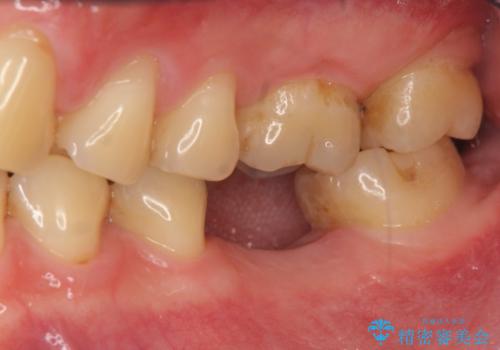

銀歯を除去して見ると内部で虫歯が再発し、歯の辺縁は破折し保存が難しく抜歯をしなければいけない状態でした。

抜歯後ブリッジとインプラント治療を検討・相談し、より周囲の歯を削らずに済むインプラント治療を希望されたのでインプラントによる機能回復を計画します。

- 46.2万円(インプラント・チタンカスタムアバットメント・仮歯・ジルコニアクラウン)費用は治療当時の料金となります